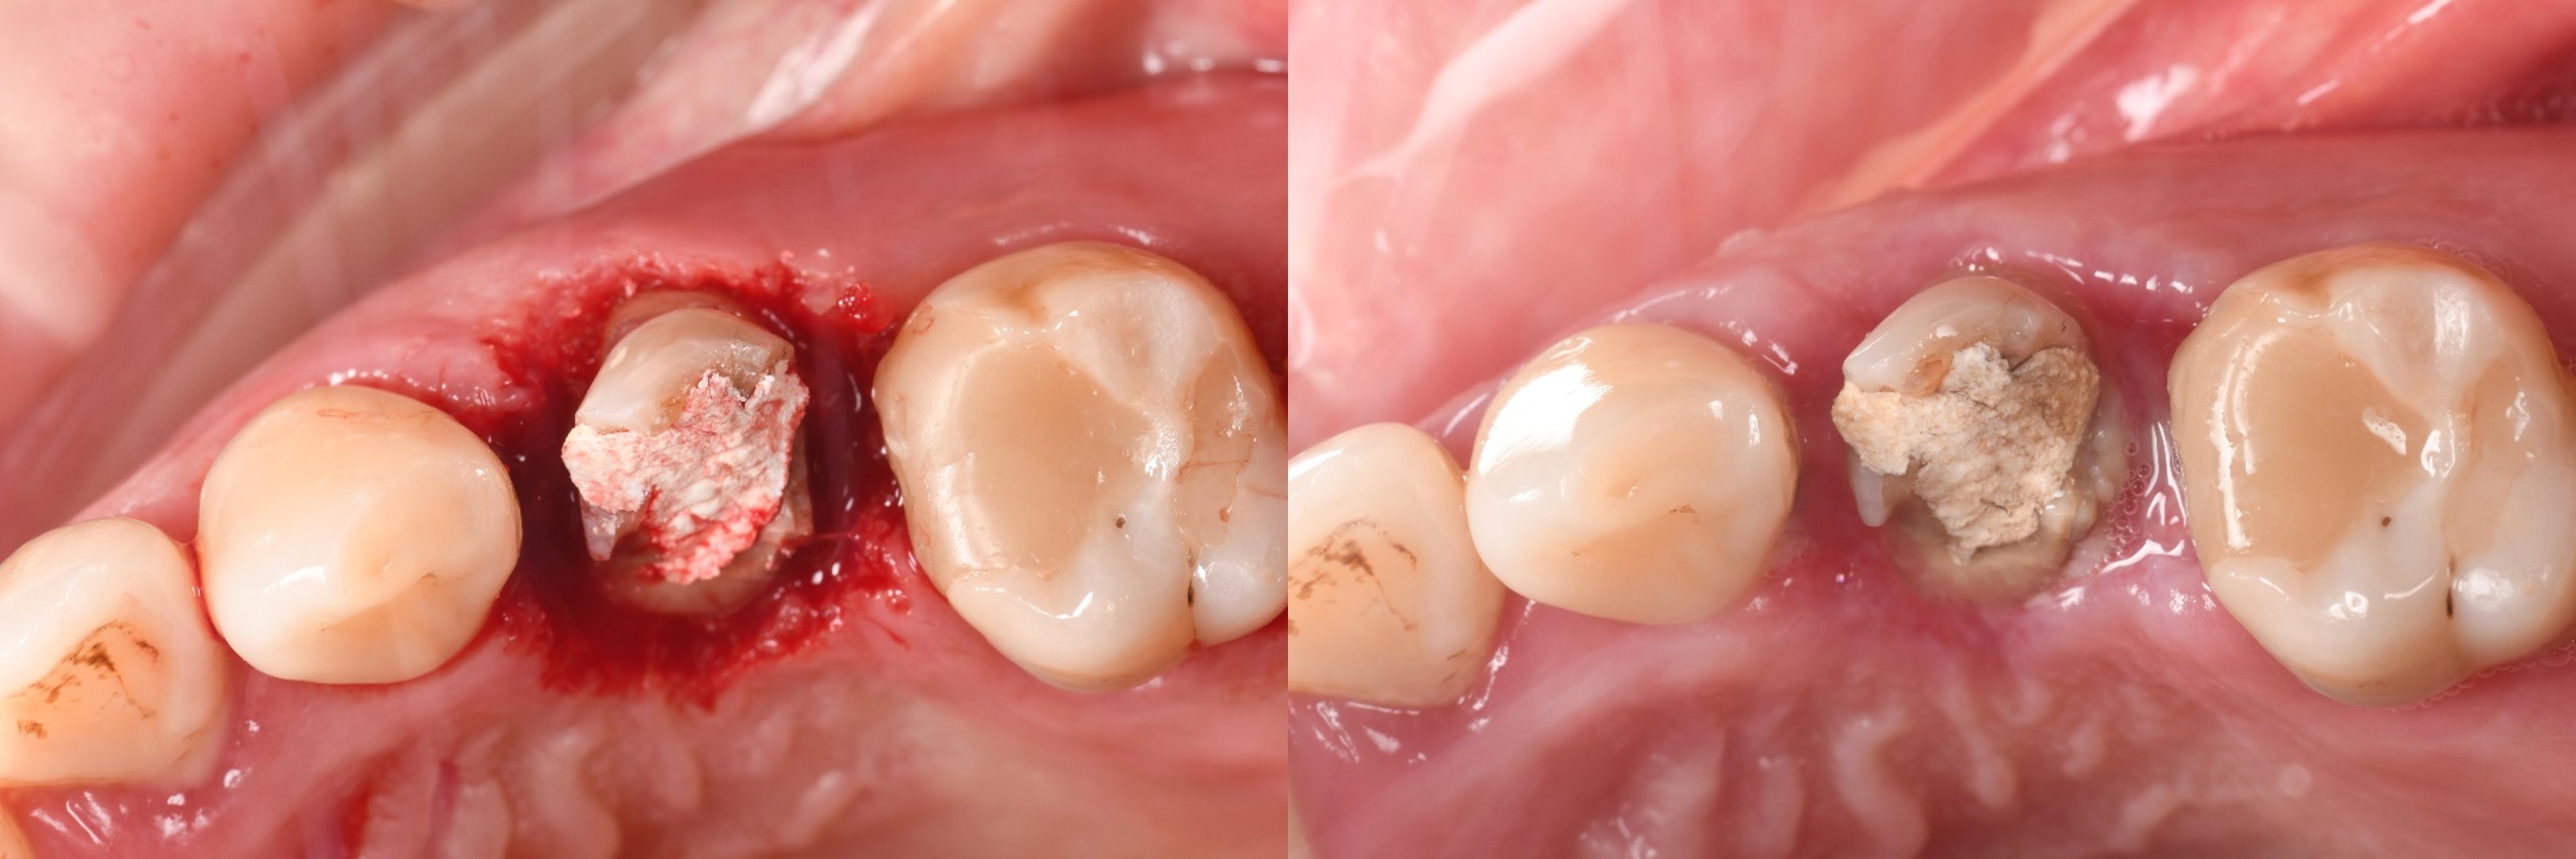

治療後,咬合良好

治療後,密合度良好

術前、術後比較